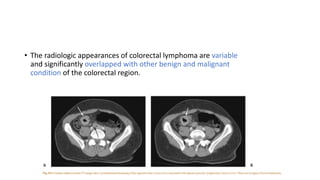

• The radiologic appearances of colorectal lymphoma are variable

and significantly overlapped with other benign and malignant

condition of the colorectal region.

• Peripheral T-cell lymphoma presents as a diffuse or focal segmental

lesion with extensive mucosal ulceration similar to that observed in

granulomatous conditions as Crohn’s disease or tuberculosis.